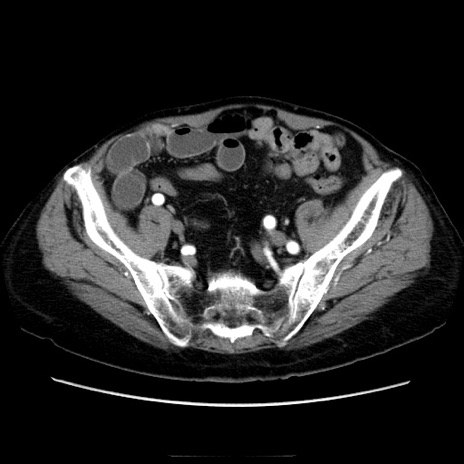

症例21(横断像)

【症例】70歳代男性

【主訴】腹痛

【現病歴】肝硬変・肝細胞癌にてかかりつけの方。約9時間前に食後より腹痛出現。症状が徐々に増悪し、嘔吐出現したため来院。

【既往歴】肝硬変、肝細胞癌(RFA、TACE後)

【身体所見】意識清明、表情苦悶様、BT 36℃、BP 129/78mmHg、P 88bpm、SpO2 97%(RA)、右上腹部から心窩部にかけて圧痛あり、反跳痛なし、筋性防御あり。

【データ】WBC 5800、CRP 0.16